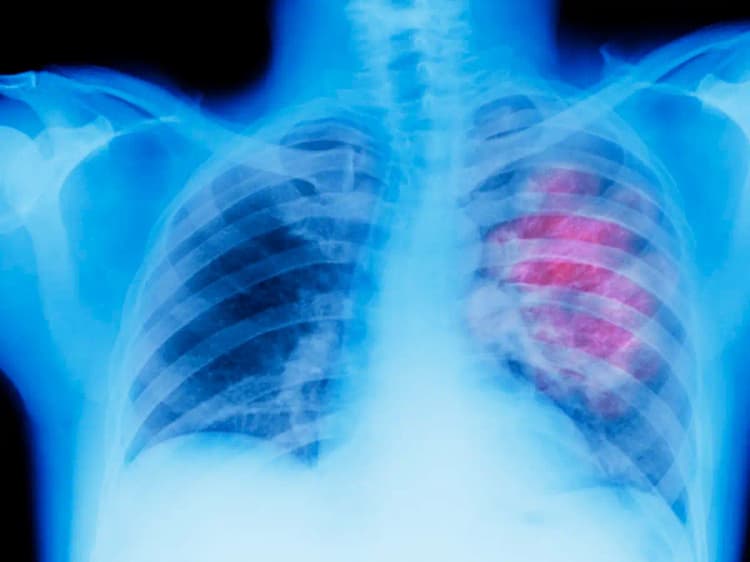

AI Chest X-Ray : हाल में विकसित कृत्रिम बुद्धिमत्ता (एआई) का मॉडल किसी के भी सीने के एक्स-रे से उसकी उम्र का आकलन कर सकता है. ‘द लांसेट हेल्दी लॉन्गेविटी’ पत्रिका में प्रकाशित नये अनुसंधान से यह जानकारी सामने आयी है. जापान के ओसाका मेट्रोपॉलिटन विश्वविद्यालय के अनुसंधान से पता चलता है कि एआई का यह मॉडल अनुमानित और सटीक उम्र के बीच के अंतर से उच्च रक्तचाप और असाध्य श्वसन रोग से संबंधित बीमारियों के बारे में संकेत दे सकता है.

उम्र के आकलन के लिए एआई मॉडल को 2008 और 2021 के बीच स्वास्थ्य जांच के लिए आये 36,051 स्वस्थ व्यक्तियों से संकलित उनके सीने के करीब 67,000 रेडियोग्राफ का इस्तेमाल कर प्रशिक्षित किया गया है.

अनुसंधानकर्ताओं ने पाया कि मॉडल एआई अनुमानित उम्र और व्यक्ति की सटीक उम्र के बीच मजबूत संबंध दिखाती है. फिर इसे ज्ञात बीमारियों वाले कई रोगियों से संकलित सीने की अतिरिक्त 34,197 रेडियोग्राफ पर एआई अनुमानित आयु और प्रत्येक बीमारी के बीच संबंध का विश्लेषण करने के लिए प्रशिक्षित किया गया.

कुल मिलाकर इस एआई मॉडल को जापान में पांच संस्थानों से 70,248 उम्मीदवारों से संकलित करीब 1,01,300 एक्स-रे (सीने के) से प्रशिक्षित किया गया. व्यक्ति की अनुमानित एआई उम्र और उनकी सटीक उम्र के बीच तुलना से उच्च रक्तचाप, हाइपरयुरिसीमिया (रक्त में उच्च यूरिक एसिड का स्तर) और श्वसन से संबंधित असाध्य रोगों जैसी गंभीर बीमारियों के बीच संबंध का पता चला. अनुसंधानकर्ताओं ने कहा कि इसका अर्थ है कि एआई द्वारा अनुमानित आयु जितनी अधिक होगी, इन व्यक्तियों में उपरोक्त बीमारियां होने की संभावना उतनी ही अधिक होगी.